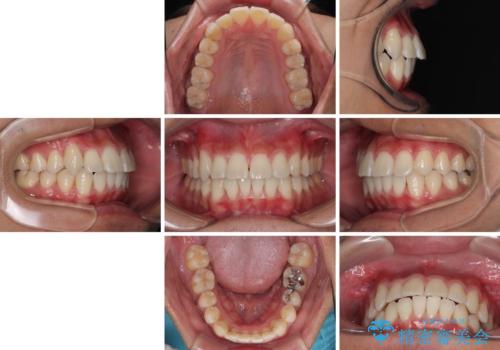

八重歯を無理なくなおしたい ワイヤー装置による非抜歯矯正治療

1年強でワイヤー装置を外すことができ、思ったよりも短期間で終了したため、患者様には大変喜んでいただきました。